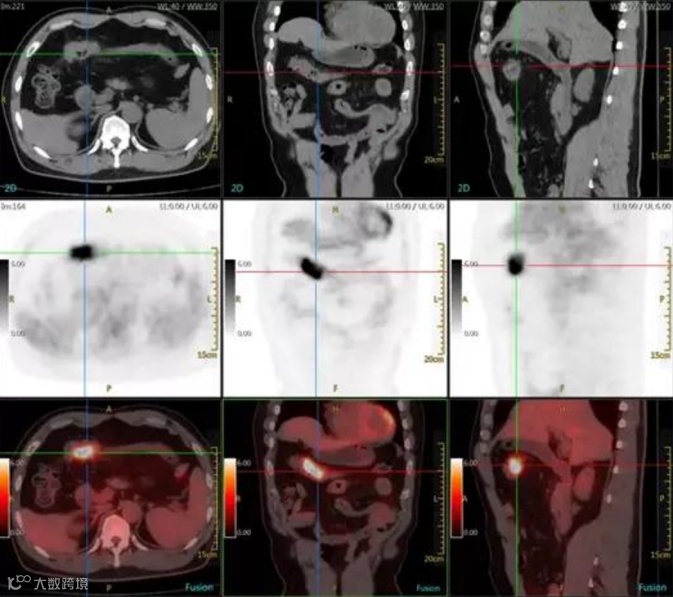

54岁男性,横结肠近段肠壁增厚,PET/CT检查提示18F-FDG代谢增高,诊断为结肠癌。疾病早期的PET/CT检查为患者进行临床治疗赢取了宝贵时间。